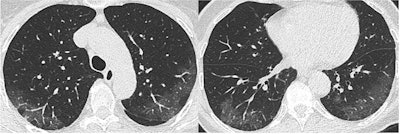

SARS-CoV-2 appears to be transmitted primarily through respiratory droplets, with a five-day median timeframe between exposure and symptoms. Thoracic CT has proven to be highly sensitive for confirming SARS-CoV-2 infection, with some studies reporting values as high as 97%, and it offers quicker results than reverse transcription polymerase chain reaction (RT-PCR) testing, according to Revel.